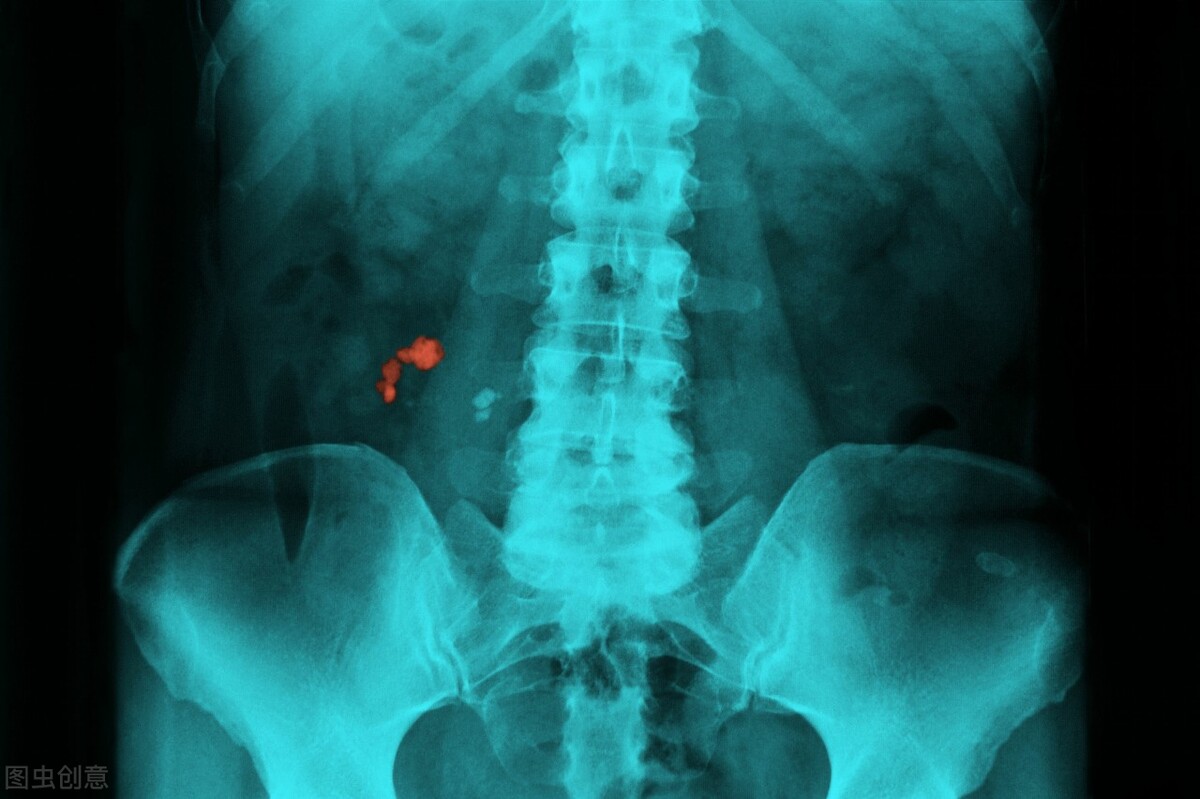

除了白血病,腰疼也可能是胰腺癌的一个症状。主要在于胰腺位于腹膜后,一旦胰腺处长出肿瘤,就容易侵犯神经丛,并引起严重的腰疼。

第三种和腰疼有关的肿瘤就是肾细胞癌,这和肾脏所在的位置有关,通常来说肾癌的腰疼是钝痛感,与此同时,还可能会伴随有尿血的出现。